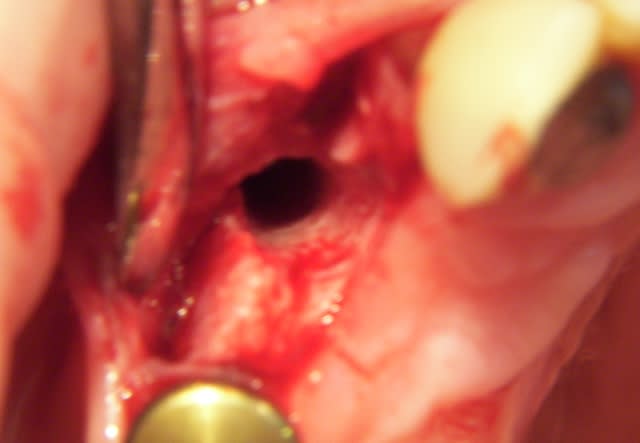

Patient de 21 ans ayant perdu une 22 lors d'un AVP en 2004. Tentative par un stomato de greffe en onlay de corail qui s'est soldée par un échec avec infection +++ et fonte osseuse aggravée.

revu le patient hier... tissus mous totalement fibrosés suite à greffe ratée et retraction cicatricielle.

Je m'oriente donc avant sur récupération d'une gencive suffisament épaisse.